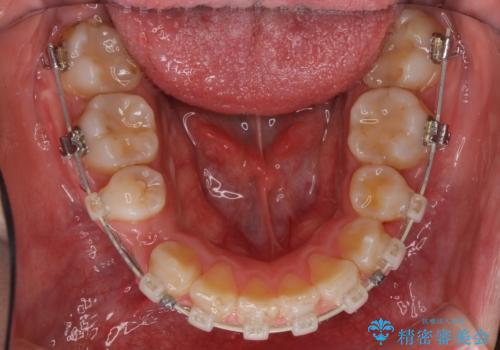

- 矯正装置

- 審美装置

- 治療期間

- 2年6ヶ月

- 治療回数

- 10-30回